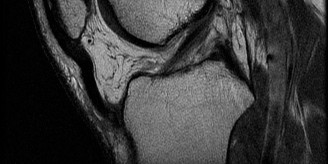

Magnetic Resonance Imaging Evaluation

Magnetic resonance imaging without contrast is the gold standard for evaluating intra-articular knee pathology. Standard sequences included T1-weighted, T2-weighted, and proton density fat-suppressed images in the sagittal, coronal, and axial planes.

- Anterior Cruciate Ligament: Sagittal T2-weighted images demonstrated a complete discontinuity of the anterior cruciate ligament fibers. The ligament appeared edematous and amorphous, with the classic "empty notch sign" visible on coronal sequences. The proximal stump of the ligament was retracted and resting horizontally within the intercondylar notch.

- Bone Bruise Pattern: Characteristic osteochondral impaction injuries, or "bone bruises," were evident as areas of hyperintensity on T2 fat-suppressed images in the middle portion of the lateral femoral condyle and the posterior aspect of the lateral tibial plateau. This kiss-lesion pattern results from the anterior subluxation of the tibia and subsequent impaction of the lateral femoral condyle against the posterolateral tibial plateau during the pivot-shift mechanism. The presence of severe bone bruising correlates with higher initial pain levels and potential long-term chondral degradation.

- Meniscal Pathology: The coronal and sagittal sequences revealed a hyperintense linear signal extending to the articular surface in the posterior horn of the medial meniscus. The morphology was consistent with a longitudinal vertical tear located in the red-white zone (peripheral third), making it a highly suitable candidate for meniscal repair. The lateral meniscus appeared intact.

- Medial Collateral Ligament: Coronal T2 sequences showed periligamentous edema surrounding the superficial medial collateral ligament, primarily at its femoral origin, with some intra-substance signal but no complete discontinuity. This confirmed the clinical diagnosis of a Grade II medial collateral ligament sprain.

- Anterolateral Complex: Edema was noted in the anterolateral soft tissues, corresponding to the radiographic Segond fracture, confirming injury to the anterolateral capsular structures.